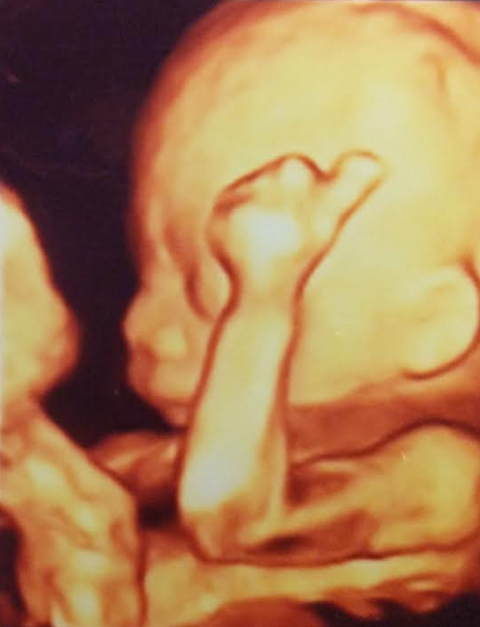

20-22 week Ultrasound . The detailed mid trimester scan is the single most important scan in pregnancy . This is the optimal time to detect fetal abnormality . Other issues such as placental site and growth will also be assessed . Generally, views of the baby are excellent and this scan is enjoyed enormously by parents .